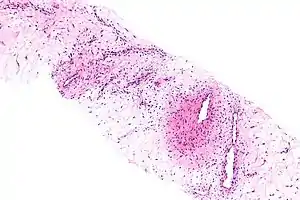

| Micrograph of an aggressive angiomyxoma. Core biopsy. H&E stain. | |

Microscopy

- Vascular appearance of tumor[8]

- Hypocellular mesenchymal lesion

- Spindled and stellate cells with an ill-defined cytoplasm

- Cells loosely scattered in a myxoid stroma

- No evidence of nuclear atypia and mitosis

- Numerous, thin-to-thick wall vessels of different sizes

- Myxoid, hypocellular background

- Bland cytological appearance of spindle cells